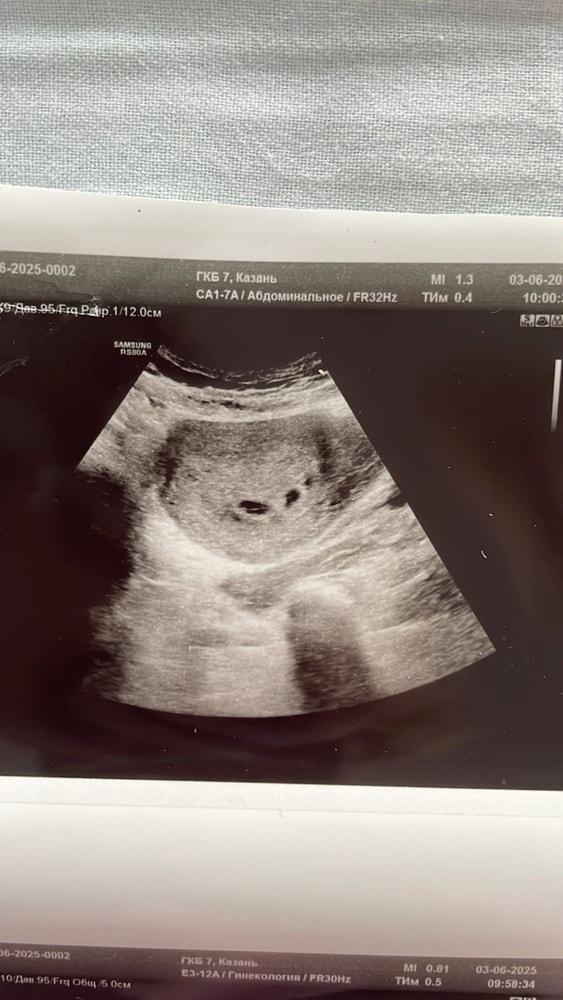

1 плодное яйцо и под ним ретрохориальная гематома

Ксеня, так вот на узи же хорошо видна гематома … странно ! Темный овал под плодным яйцом